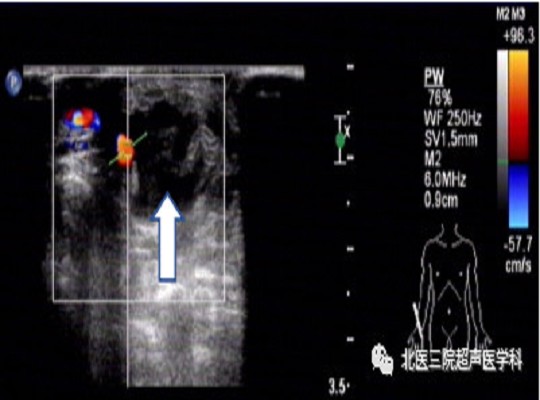

头静脉瘤样扩张